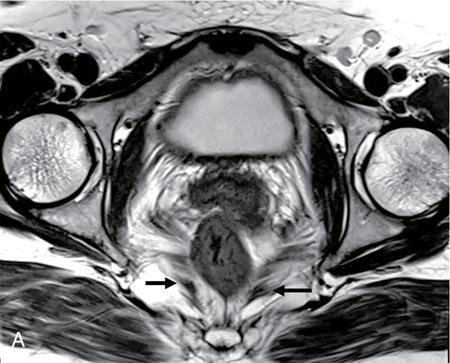

PELVIC FLOOR IMAGING – ANTERIOR AND MIDDLE COMPARTMENTS Anu Epean, Deepa Korula The term ‘Pelvic floor disorder’ refers to dysfunction of the pelvic floor musculature and connective tissues which provide support for the pelvic organs. This can produce a wide range of symptoms such a urinary incontinence, straining to void, dyspareunia, constipation, faecal incontinence and organ prolapse. The greatest risk factors for pelvic floor disorders are female sex and advanced age. Other risk factors include obesity, pregnancy, multiparity, smoking, connective tissue disorders. The pelvic floor is broadly divided into three compartments. The bladder and urethra form the anterior compartment. The vagina and uterus form the middle compartment and the posterior compartment comprises of the rectum and anal canal (Fig. 7.16.1.1). The attachment of the fascia, muscles and the ligaments to the bony pelvis form the support for these structures. From cranial to caudal, there are three layers which make up the pelvic floor – the endopelvic fascia, the pelvic diaphragm and urogenital diaphragm. This is the most cranial layer of pelvic floor, lying deep to peritoneum. It is a fine structure, comprising of a network of connective tissue which encases the pelvic viscera, provides support to the pelvic organs and maintains their anatomic relationship. There are several condensations of this fascia and ligaments which provide support in each of the pelvic compartments. In the anterior compartment, a fascial condensation called pubocervical fascia extends from anterior vaginal wall to the pubis. Tear in the pubocervical fascia can cause cystocele and urinary incontinence. There are three groups of ligaments which provide urethral support – periurethral, paraurethral and pubourethral ligaments. The periurethral ligaments arise from medial fibres of pubococcygeus and pass ventral to urethra. The paraurethral ligaments connect the lateral wall of urethra to periurethral ligament and pubourethral ligament connects the lateral wall of urethra to arcus tendineus. The urethra lies on a Hammock-like supportive layer of endopelvic fascia and anterior vaginal wall, which are stabilized by attachment laterally to arcus tendineus and levator ani (Fig. 7.16.1.2). In the middle compartment, condensations of the endopelvic fascia which attach the uterus to the lateral pelvic wall is called parametrium, which is made up of the uterosacral and cardinal ligaments. The uterosacral cardinal ligament complex supports and suspends the cervix and upper vagina above the levator plate. More inferiorly, the paracolpium attaches the vagina to the lateral pelvic wall. There are three levels of fascial support to the vagina: In the posterior compartment, the perineal body located within the rectovaginal septum supports ligaments and muscles and prevents abnormal widening of levator hiatus (Fig. 7.16.1.3). The rectovaginal fascia extends from posterior wall of vagina to anterior rectal wall. A tear in the rectovaginal fascia is the cause for an anterior rectocele. Arcus tendineus levator ani (ATLA) is formed by the condensation of the endopelvic fascia laterally, along the pelvic sidewall. This extends obliquely from inferior pubic symphysis to ischial spine and provides lateral support to the pelvic organs and attachment of the levator ani. Fascial condensations are not visualized on imaging; however, organ prolapse, due to deficiency in any of these, can be detected on MRI. The levator ani and the coccygeus muscles make up the pelvic diaphragm. The levator ani is the primary muscle of the pelvic diaphragm and is attached to the pubis and to the ATLA laterally on both sides. The slow twitch fibres of the levator ani continuously contract, maintaining tone to the pelvic floor and suspending the pelvic organs in the correct position. The two most important components of the levator ani are the iliococcygeus and puborectalis muscles. The iliococcygeus arises from external anal sphincter and has a curved shape, concave inferiorly. It fans out laterally to its insertion in the posterior part of arcus tendineus (Fig. 7.16.1.4A and B). Posteriorly, in the midline, condensations of ilococcygeus form a firm raphe anterior to coccyx called the anococcygeal ligament or levator plate. The pubococcygeus muscle is a component of the levator ani. It forms the anteromedial part and is a thick bundle of fibres arising from the pubis and anterior portion of arcus tendineus. It extends horizontally back to behind the rectum, medially forming the margin of urogenital hiatus (Fig. 7.16.1.5A). The anorectal and urogenital hiatus are closed by the contraction of the pubococcygeus muscle. This enables support during rest and in situations where the intraabdominal pressure is increased. The medial fibres of pubococcygeus, depending on their attachment to urethra, vagina, anus and rectum are termed as pubourethralis, pubovaginalis, puboanalis and puborectalis, collectively as pubovisceralis. The puborectalis forms a sling around the rectum (Fig. 7.16.1.5B). The muscles of the pelvic diaphragm are well delineated on MRI. The urogenital diaphragm or perineal membrane is the most caudal layer of the pelvic floor. It has a triangular appearance, extending from the pubic symphysis and the ischiopubic ramus to the posterior perineal body. It is ventral to the external anal sphincter and perineal body. It is attached to the surrounding structures such as the perineal body, external anal sphincter, vagina and the bulbocavernosus muscle. Imaging has an increasing role in the evaluation of pelvic floor disorders. Clinical examination alone has a low sensitivity and specificity for the detection of multicompartment involvement and organ prolapse. Imaging helps to detect involvement of multiple pelvic compartments and thus to plan surgery. Ultrasound, MRI and conventional imaging which includes voiding cystourethrography, evacuation proctography and dynamic cystocolpoproctography (DCP) are used to evaluate the pelvic floor. It is easily available, cheap and does not involve ionizing radiation. In the evaluation of the anterior compartment, ultrasound is more reliable than MRI. Transperineal ultrasound using 2D, 3D or 4D techniques along with dynamic imaging helps to evaluate pelvic floor dysfunction. Patient is placed in a dorsal lithotomy position for a transperineal scan although a standing position can also be used. Convex transducer (2–6 MHz) or endoluminal transducers (endovaginal/endorectal) maybe used. In a midsagittal translabial scan, the anatomic relationship of urethra, bladder, vagina, cervix and anorectum can be studied and the relative position of these organs determined by use of certain measurements. The bladder-symphysis distance (BND) is the distance between the bladder neck and lowest margin of symphysis pubis and demarcates position of the bladder neck. Measurement of BND is made at rest and during Valsalva manoeuvre and the difference in BND between the two, gives the measure of bladder neck descent. There are no definite values to indicate normal descent but there is a proposed cut off of 20, 25, 30 mm to indicate hypermobility (Fig. 7.16.1.6A and B). The proximal urethra rotates posteroinferiorly during Valsalva manoeuvre and this can be measured by the posterior urethrovesical angle (β) or the gamma angle. The posterior urethrovesical or retrovesical angle (β) is the angle between a line through the urethral axis and the line through the trigonal surface of the bladder and varies from 90–120 degrees normally. This may increase to 160–180 degrees and can be associated with funnelling of bladder neck. The gamma angle is the angle between a line through the inferior margin of pubic symphysis and the urethrovesical junction. This is seen on Valsalva manoeuvre or at rest in patients with stress incontinence (Fig. 7.16.1.7). Color Doppler can demonstrate urine leakage on performance of Valsalva or at rest. Other abnormalities that can be detected on transperineal ultrasound are cystocele, urethral diverticulum, Gartner duct cyst, foreign body or bladder tumour. 3D pelvic ultrasound is useful to evaluate pelvic floor dysfunction and to study the urethra, levator ani complex, paravaginal supports, prolapse and implant imaging. 4D ultrasound helps in real-time, dynamic imaging of pelvic floor. In the middle compartment, although uterine prolapse is often clinically evident, it can also be detected by ultrasound. Uterine prolapse can be also quantified by measuring maximum descent of uterus from the reference point which is the inferior margin of pubic symphysis. Ultrasound is also useful to evaluate for surgical planning in a large retroverted uterus with an anteriorly placed cervix causing voiding symptoms. MRI is useful in the evaluation of pelvic floor as it provides good anatomic detail about the pelvic floor muscles, ligaments because of its inherent superior soft tissue resolution. In addition, dynamic MRI yields functional information. MRI defecography is a dynamic study performed to study the posterior pelvic compartment but it also gives information about the anterior and middle compartments. It can be performed both with closed magnet and open magnet systems. The patient is positioned supine with phased array coil around pelvis in a closed magnet system. In an open magnet system, the patient is in a sitting and more physiological position; however, due to the lower signal to noise ratio and lower resolution, a closed magnet system is preferred. Bowel preparation with use of laxative on night before the scan is optional. Voiding prior to the study is encouraged since an overdistended bladder can cause misinterpretation of results. Presence of some urine in the bladder is however, helpful to detect anterior vaginal prolapse. Instructions are given to the patient, prior to the procedure, about the ‘rest’, ‘squeeze’, ‘strain’ and ‘defecate’ phases of dynamic imaging, to ensure that movement or lifting of the pelvis does not occur during these manoeuvres. The rectum is filled with up to 200 mL of ultrasound gel. The patient is made to wear an adult diaper and covered with an incontinence pad on the gantry. Vaginal gel, ∼50 mL maybe introduced since this helps to delineate anatomic landmarks and detect uterovaginal prolapse. Initial large FOV T1 localizer scans help to identify the midline sagittal section of pelvis. T2-weighted fast spin echo, high-resolution sequences in sagittal, axial, coronal planes are used to obtain anatomic detail. This is followed by dynamic imaging of the pelvic floor with use of steady state imaging sequences such as True fast imaging with steady state precession (TrueFISP Siemens) and balanced fast field echo (balanced FFE Philips). Steady state sequences have the advantage of short acquisition times and higher signal to noise ratio and hence useful to obtain rapid serial midsagittal images while patient performs ‘squeeze’, ‘strain’ and ‘defecates’. There are several points and lines for measuring and staging pelvic organ prolapse on MRI; however, the PCL line is said to have the highest interobserver and intraobserver reliability of MRI measurements compared to all proposed reference lines and is described below: Pubococcygeal line (PCL): defined as the line that connects the inferior portion of the pubic symphysis to the last coccygeal joint. The PCL is the most commonly used reference line for the assessment of pelvic floor disorders (Fig. 7.16.1.8).